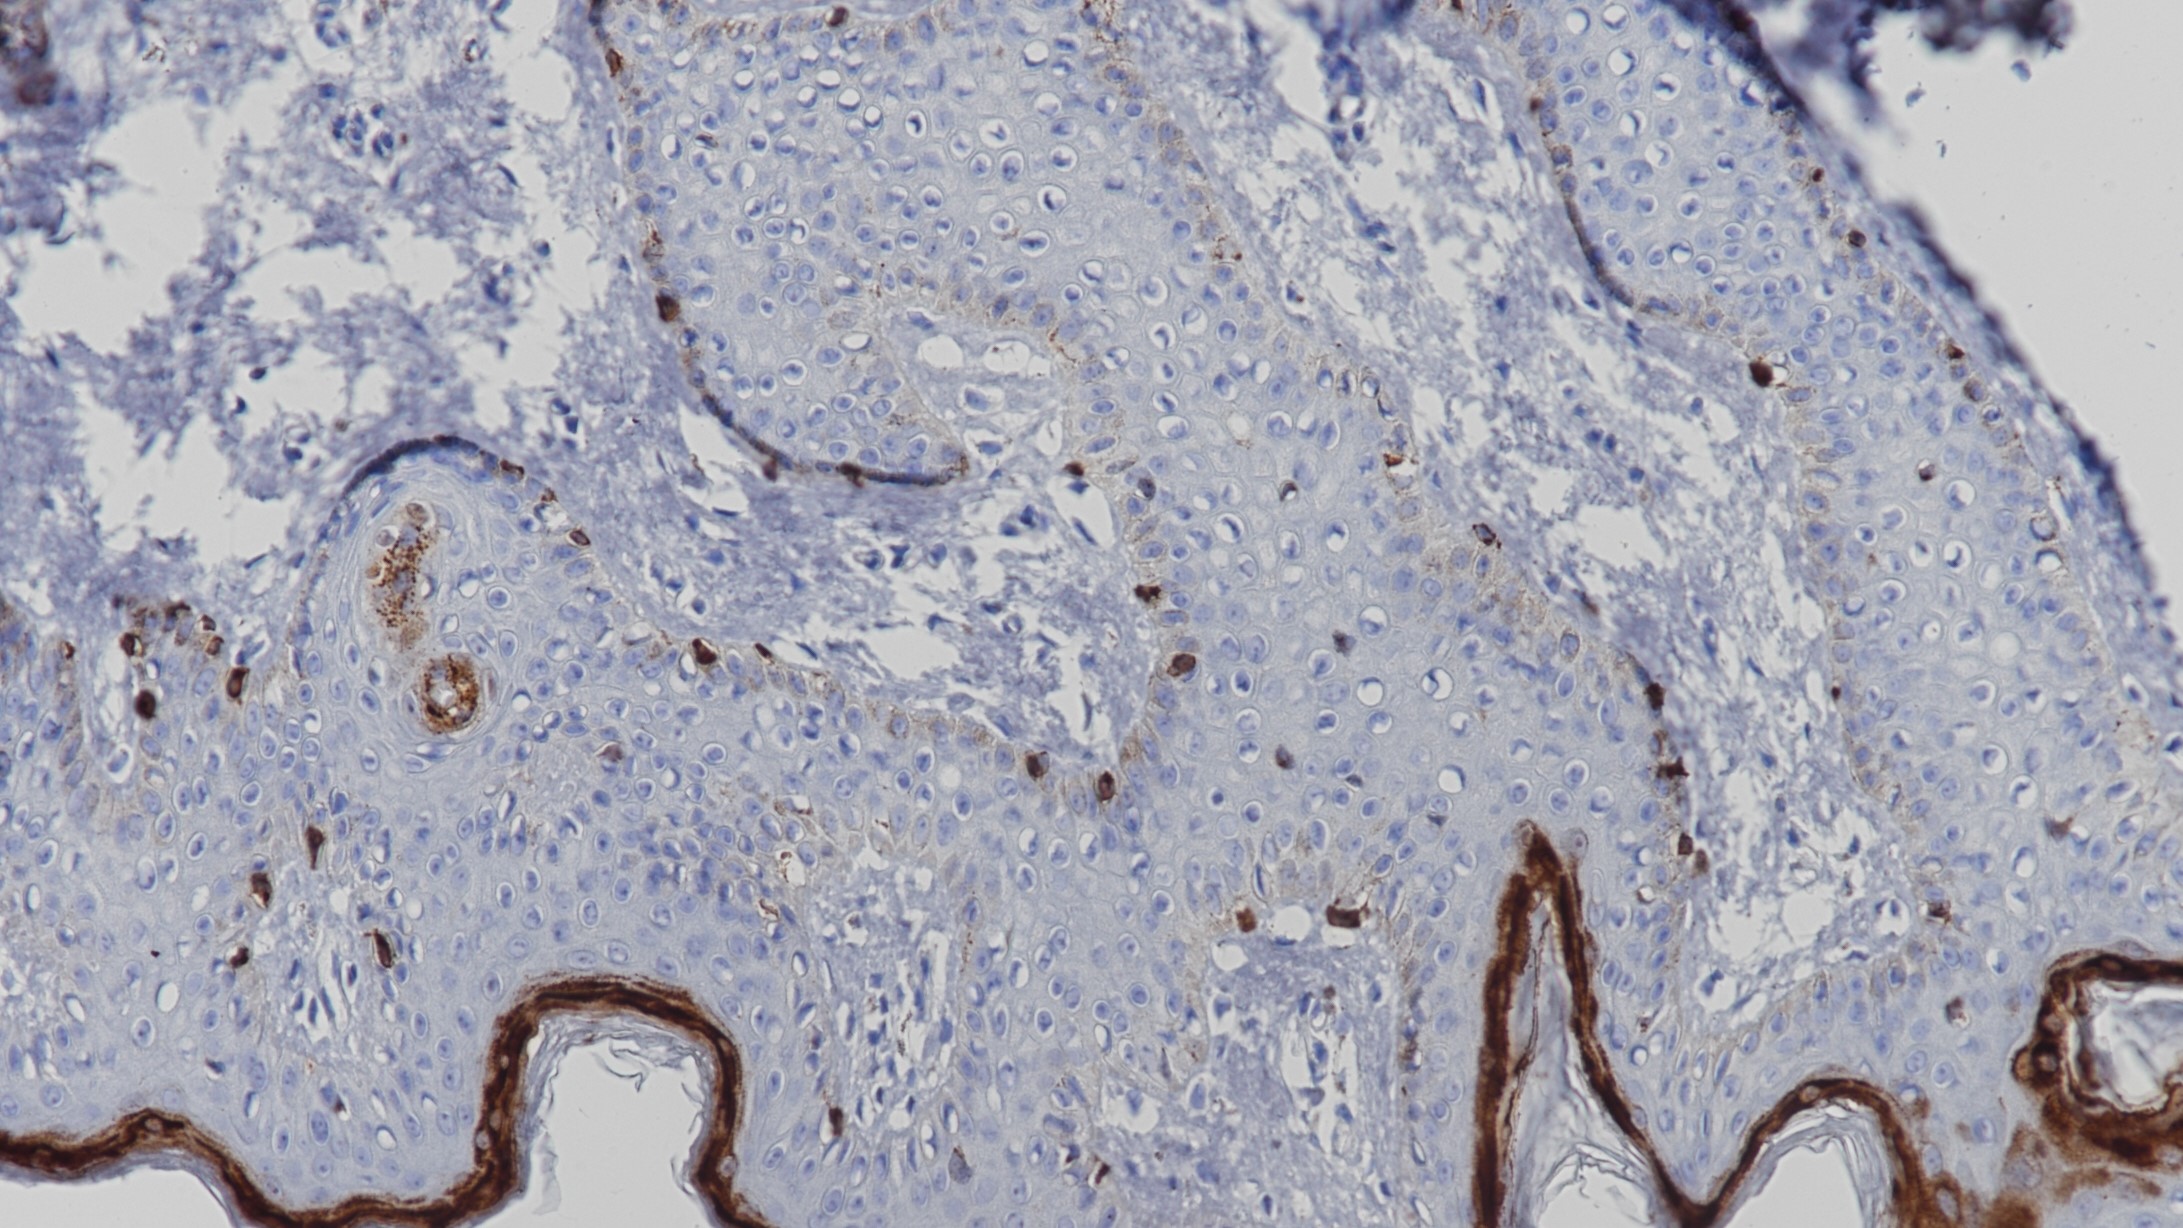

1. Jungbluth A A , Busam K J , Gerald W L , et al. A103: An anti-melan-a monoclonal antibody for the detection of malignant melanoma in paraffin-embedded tissues[J]. American Journal of Surgical Pathology, 1998, 22(5):595-602.

2. Busam K . Expression of Melan-A (MART 1) in benign melanocytic nevi and primary cutaneous malignant melanoma[J]. Am J Surg Pathol, 1998, 22.